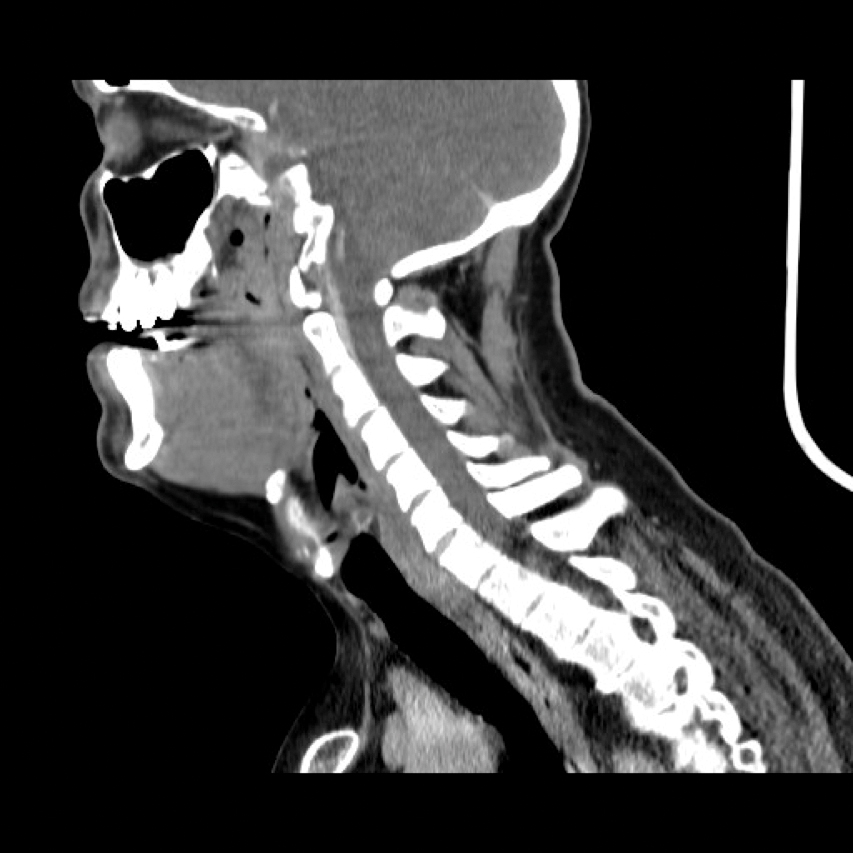

Submandibular haematoma with airway obstruction following a warfarin overdose

Submental and submandibular abscesses are frequent in oral and maxillofacial surgery; on the other hand submandibular haematomas are uncommon. However, we encountered a submandibular haematoma, initially masked as a Ludwig’s angina, which was compromising the airway of a warfarinised patient...